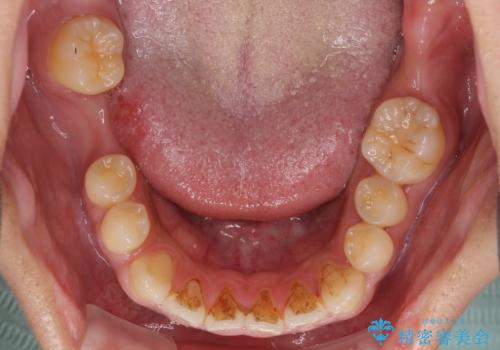

- ソーシャルメディアでのゲームに夢中になっている最中に車と接触し、前歯の抜歯を余儀なくされた患者様です。

初診時では前歯が保存できる可能性も模索しましたが、損傷が激しく3歯を抜去することとなりました。

保存となった隣在歯も神経が失活していており、補綴治療が必要であったので、オールセラミッククラウンにて補綴治療することとしました。

奥歯には元々欠損があり、欠損に伴う咬合不正も認められたため、部分矯正を行った上でインプラント補綴治療も行うこととしました。